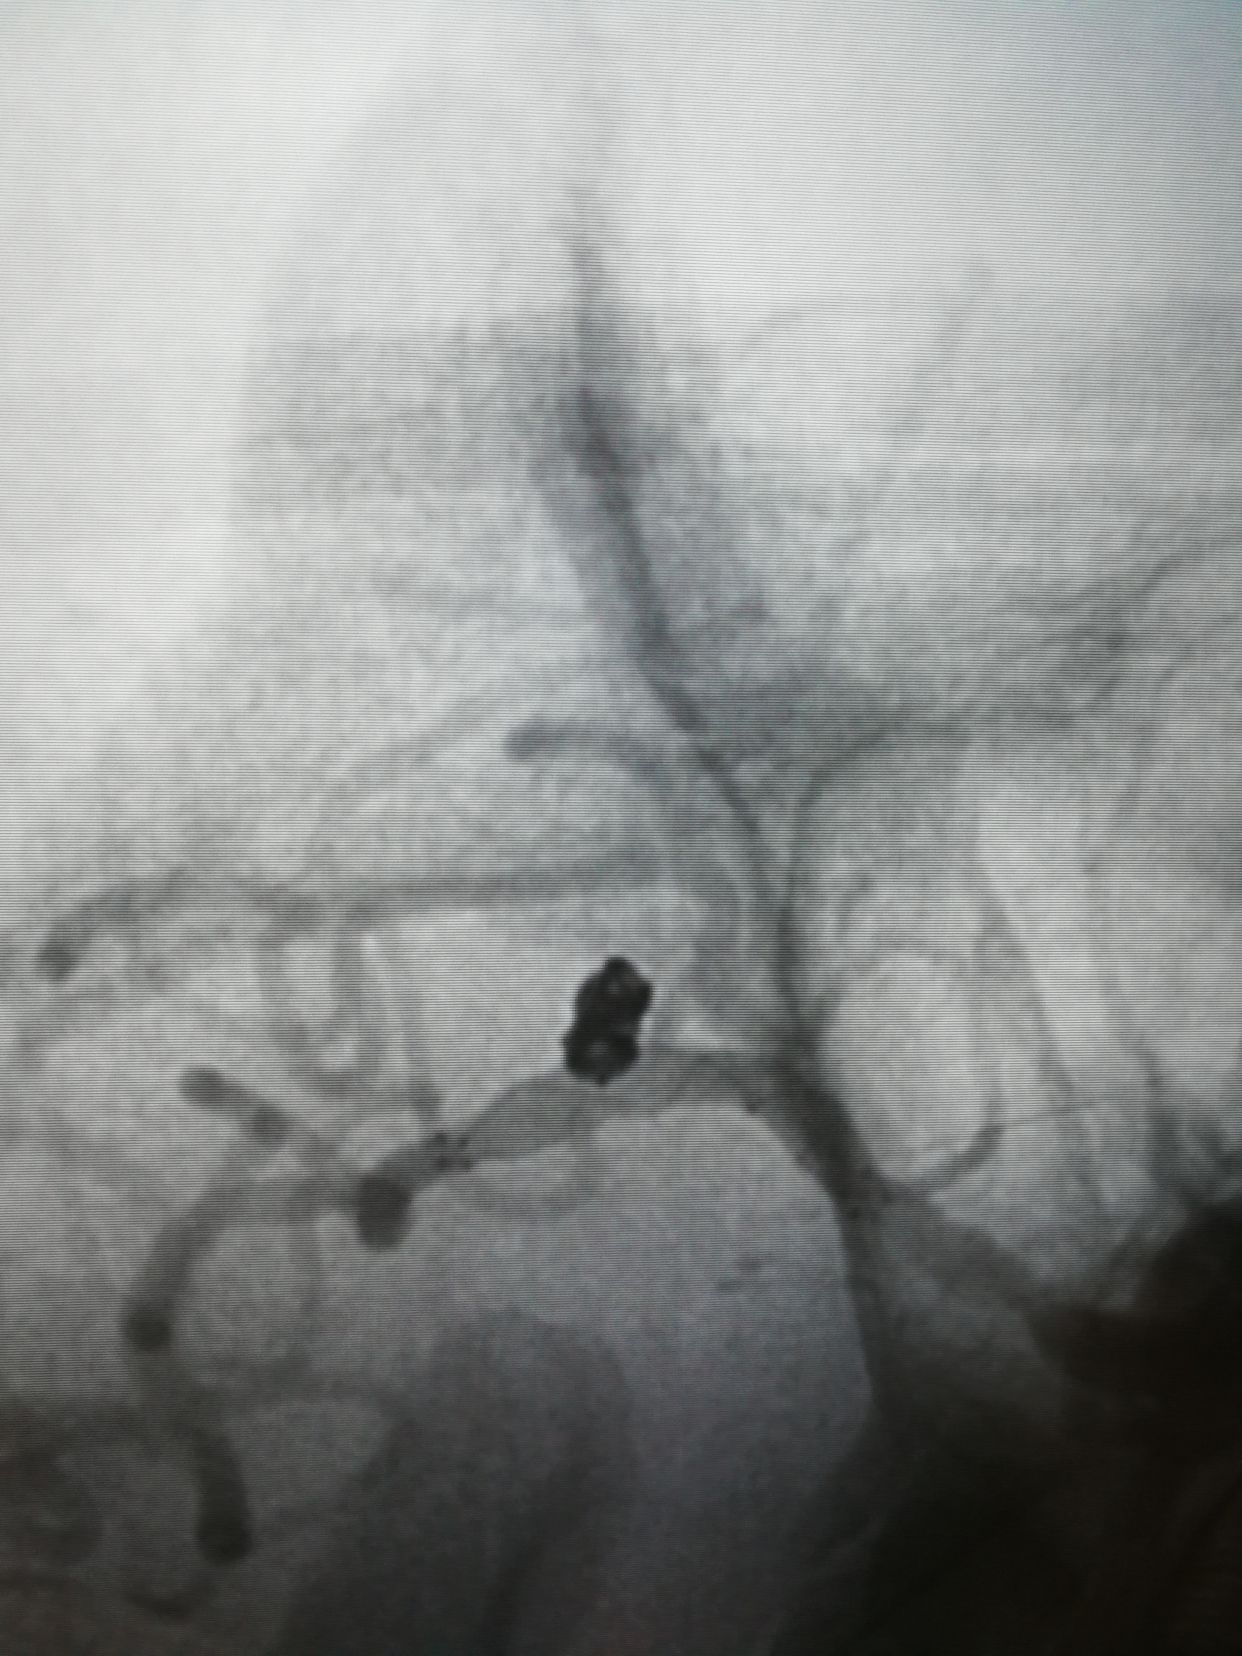

6f90cm长鞘,105navien到位。

comos 3-6,hypersoft 1.5-3填塞后,成篮还不错,下干几个袢,支架后释放很放心